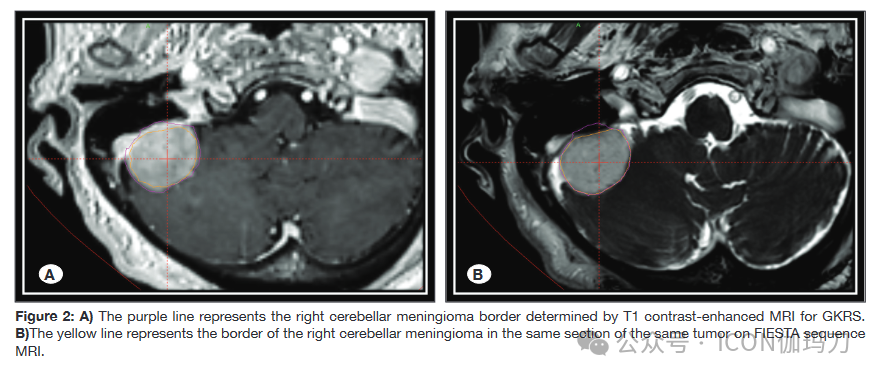

回顾了2020年1月至2022年6月在Pamukkale大学接受GKRS (Leksell伽玛刀®Perfexion™)治疗的102例脑膜瘤患者的MRI图像。按照建议使用T1+C MRI序列进行GKRS定位。此外,FIESTA MRI检查使用指定的参数(重复时间/回时间,6,7/2,8 msec;FA 60°;320 x256矩阵;厚,2mm;相交间隙,0 mm;视240X240 mm)。先前接受过手术或其他治疗(如放疗)的患者被排除在研究之外,因为他们的纳入可能会损害评估的MRI图像的评估。因此,我们回顾性地回顾了54例首次行GKRS的单发脑膜瘤患者的资料。将患者分为两组:1组为伴静脉窦的脑膜瘤(Sindou I-VI型)(35例),2组为无静脉窦侵的脑膜瘤。由于硬脑膜静脉窦的高且均匀的对比增强可能显示与邻近脑膜瘤相似,从而使靶体积增大。因此,我们决定单独对脑膜瘤合并静脉窦侵进行研究。此外,我们还检查了人口统计学数据、肿瘤体积(T1+C和FIESTA MRI序列)和肿瘤的解剖位置,如图1和2所示。

1:A)紫色线代表右侧矢状旁脑膜瘤边界,由T1增强MRI检测GKRS。B)黄线为FIESTA序列MRI同一肿瘤同一层面右侧矢状旁脑膜瘤边界。